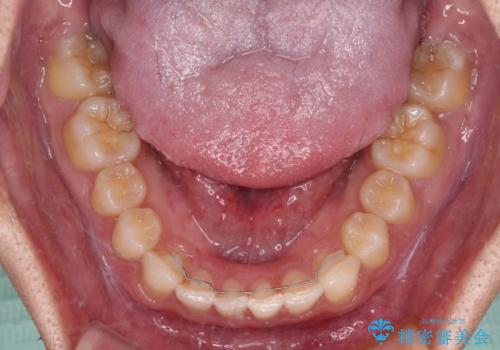

著しいディープバイトと隙間だらけの歯列

顕著なディープバイトのため、頻繁に装置が脱離することがあり、治療期間が想定よりも長くかかることがありますが、当初の予定期間で無事に治療を終えることができました。

- 矯正治療後の保定が不十分だと後戻り(元の位置に戻ろうとする動き)をします